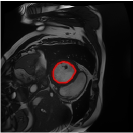

From the above discussions, we have discovered the significant potential of applying Retinex theory to image segmentation and explored its fundamental differences from traditional models. Traditional image segmentation models typically focus on the impact of intensity information on the segmentation results. Therefore, when faced with complex segmentation scenarios, the segmentation results are often affected by lighting, artifacts, and unclear boundaries in the image. As shown in Fig. 1, we present the results of the classical local model LIF [ZHANG20101199] for segmenting brain tumor images along with surrounding tissue edema. The irregular ring-like enhancement caused by the edematous tissue leads to irregular boundaries and low contrast in the images. Consequently, the LIF model can only identify the central necrotic and liquefied regions of the tumor, failing to detect the boundaries and becoming trapped in local minima. In this paper, we draw inspiration from the Retinex theory, which is widely applied in the field of image enhancement. According to Retinex theory, the reflectance component characterizes the intrinsic structural properties of the observed image and preserves texture information independent of illumination variations. By integrating this reflectance component into the level set framework, our model achieves robust segmentation of medical images even under severe intensity inhomogeneity. In addition, a linearized Structural-Prior is proposed to restore intensity consistency and capture local geometric features, thereby improving boundary localization in complex or blurred regions. Furthermore, a relaxed binary level set representation is employed to enhance robustness against noise and to enable accurate tracking of complex contours. Based on these innovations, we propose a novel variational reflectance-based level set model (RefLSM) that simultaneously corrects bias fields and performs segmentation. Experimental results demonstrate that RefLSM significantly outperforms conventional level set methods in both segmentation accuracy and robustness. We present the results of our model segmenting the two brain tumor images mentioned above in Fig. 2.